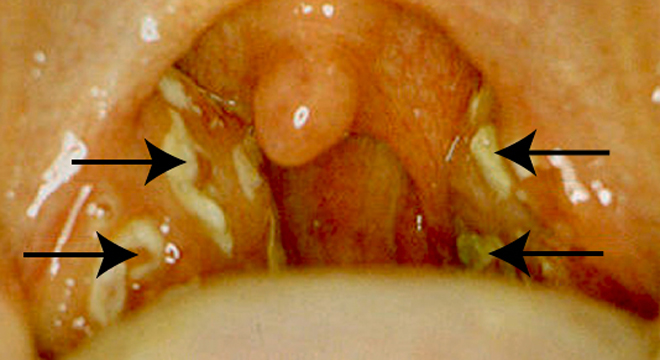

• Die Mandeln sind gerötet, geschwollen und haben streifige oder punktförmige Eiterstippchen

Eine häufige Komplikation der eitrigen Angina ist der Peritonsillarabszess (eine Eiteransammlung im Tonsillenbett), im schlimmsten Fall gefolgt von einer Venenthrombose der Halsvene. Das ist ein Notfall und gehört sofort in ärztliche Behandlung. Der Abzess muss operativ entfernt werden. In der gleichen Sitzung werden meist auch die Mandeln mit entfernt (Tonsillektomie).